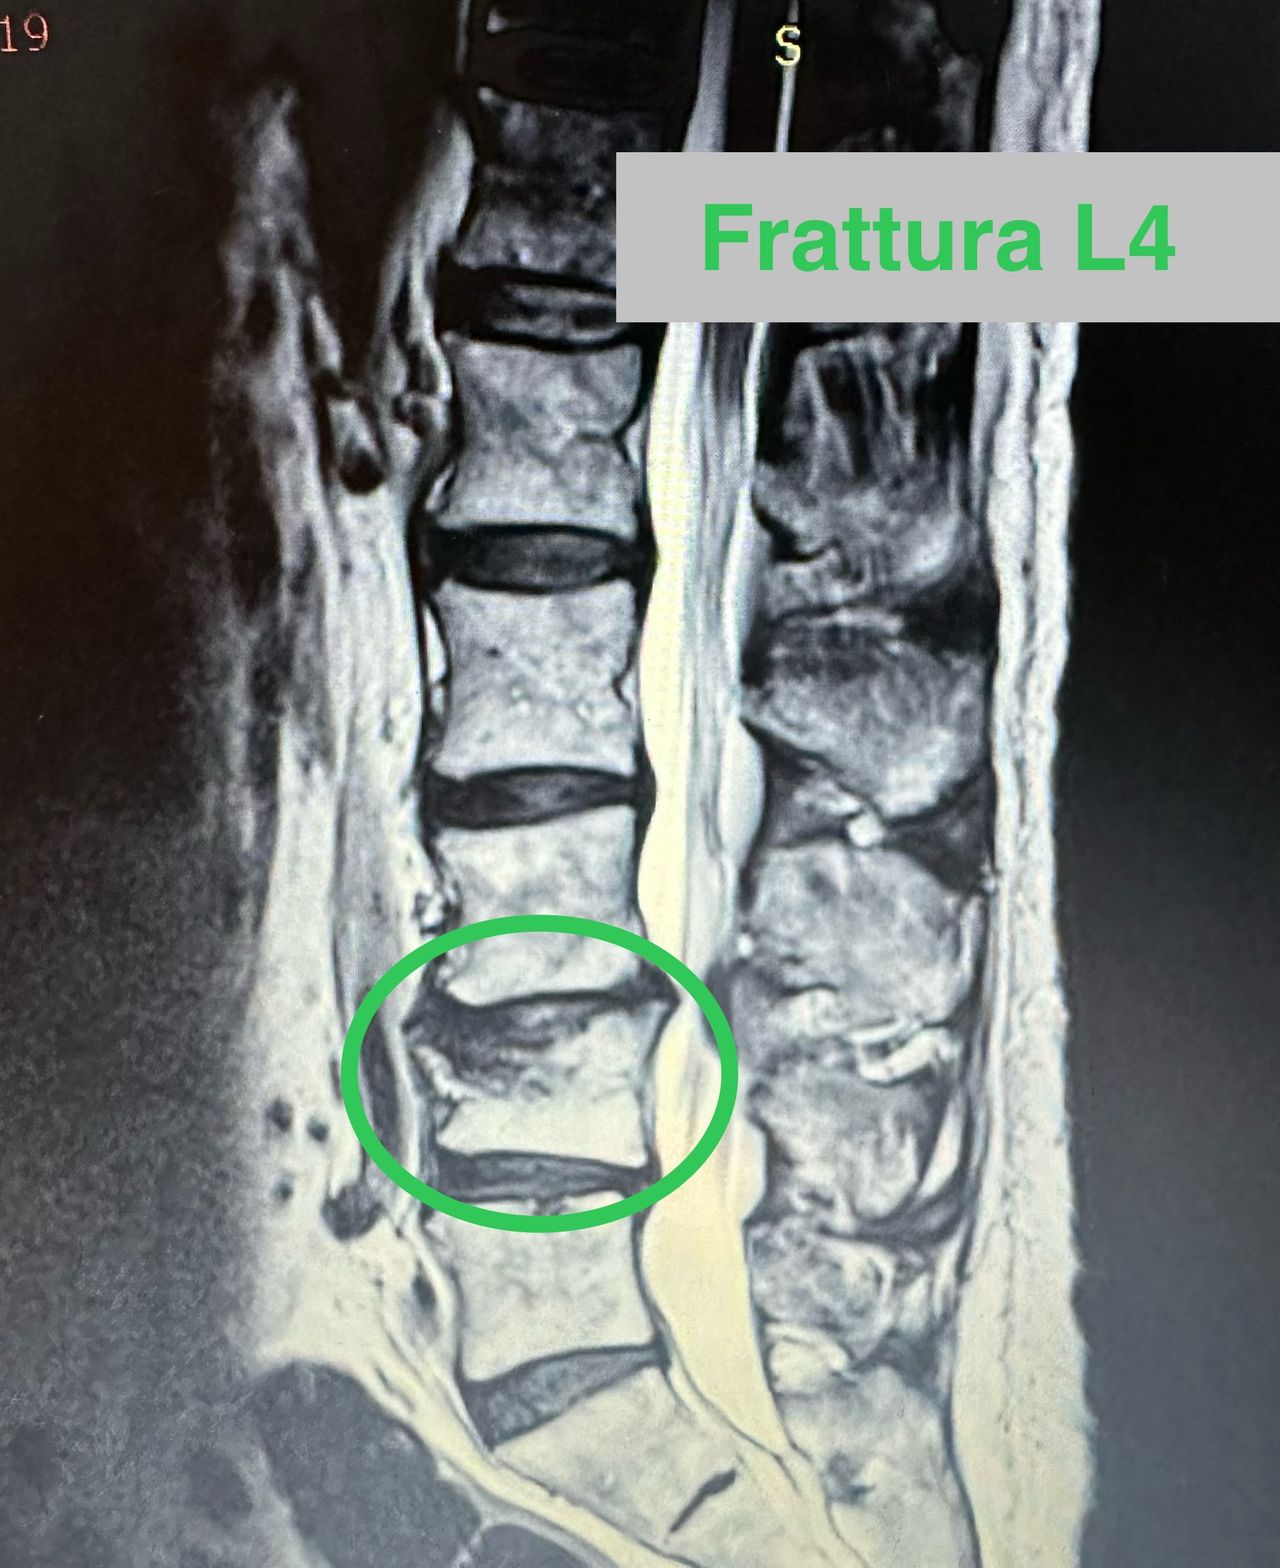

- Chirurgia Mininvasiva percutanea vertebrale - stabilizzazioni e artrodesi intersomatiche (per fratture vertebrali, spondilolistesi, instabilità vertebrali, discopatie)

- Vertebroplastica e cifoplastica percutanea (fratture vertebrali)